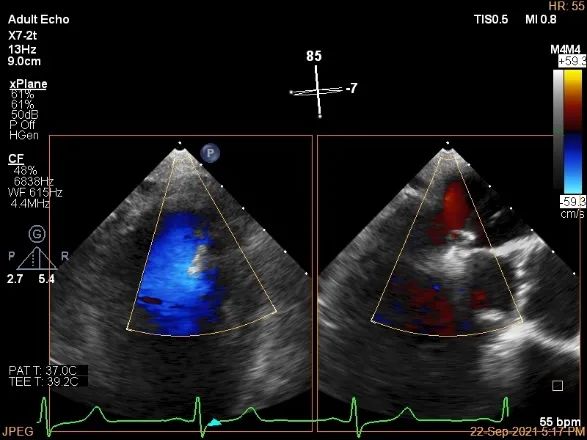

患者麻醉方式为全麻,建立静脉通路后,穿刺右侧股静脉,预埋ProGlide缝合器,食道超声指导下房间隔穿刺成功,将Superstiff导丝送至左房,应用18F鞘管扩张穿刺部位,沿导丝将导引导管送入左房,MitraClip调整后顺利到达二尖瓣目标位置,在食道超声辅助下,将Mitraclip NTR成形夹精确定位后,成功夹合二尖瓣A1-P1区,超声显示反流明显减少,多切面证实夹合组织充分,肺静脉多普勒波形由反向恢复正常,手术顺利结束,安返普通病房。

计算前叶捕获长度9mm,后叶捕获长度7mm。

夹子夹闭后,未见明确残余分流

3d-color确认残余分流情况